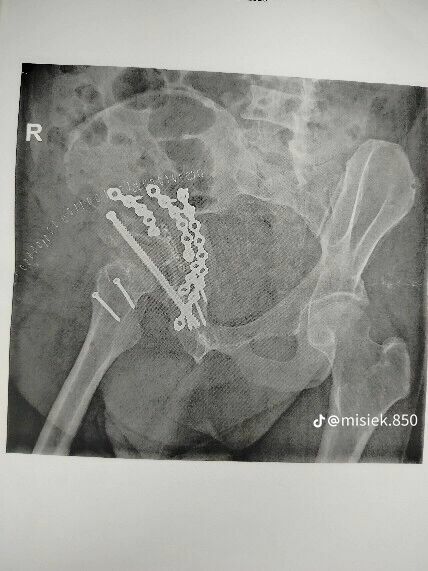

Niestety, jako pasażer uczestniczyłem w bardzo ciężkim wypadku samochodowym, który pozostawił mnie z poważnymi obrażeniami. Leczenie i rehabilitacja są kluczowe dla mojego powrotu do zdrowia, ale wiążą się z wysokimi kosztami, które przekraczają moje możliwości finansowe.